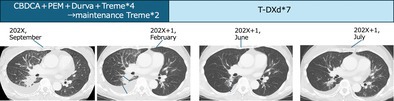

一名携带HER2 V659E突变的67岁转移性肺腺癌患者接受了曲妥珠单抗德鲁西替康(T-DXd)作为二线治疗。V659E突变是位于HER2跨膜结构域的罕见突变。在该患者中观察到的抗肿瘤效果与之前的2期试验中报道的效果相当,在2期试验中,大多数患者在激酶结构域发生突变。在这里,我们介绍详细的临床过程,并从分子生物学的角度讨论结果。

A 67-year-old patient with metastatic lung adenocarcinoma harboring a HER2 V659E mutation received trastuzumab deruxtecan (T-DXd) as second-line treatment. The V659E mutation is a rare alteration located in the transmembrane domain of HER2. The antitumor effect observed in this patient was comparable to that reported in a previous phase 2 trial, in which most patients had mutations in the kinase domain. Here, we present the detailed clinical course and discuss the findings from a molecular biological perspective.